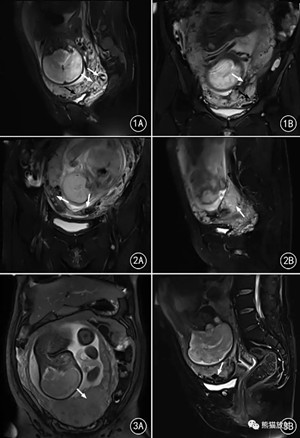

圖1 31歲,子宮下段胎盤植入,部分胎盤組織穿透下段前壁及部分左側(cè)壁,膀胱壁局部受累。A.矢狀位T2WI( HASTE) 序列顯示子宮下段膨隆伴局部胎盤增厚及子宮肌層與胎盤交界面消失( 白箭) ,胎盤-膀胱頂壁局部分界不清,膀胱壁結(jié)節(jié)狀突起( 黑箭) ; B.冠狀位T2WI 顯示胎盤內(nèi)低信號( 白箭) 、胎盤局部血管增多( 黑箭) 。

圖2 31歲,死胎,胎盤廣泛植入子宮下段肌層。A.冠狀位T2WI 顯示胎盤內(nèi)多發(fā)低信號( 箭) ,子宮-肌層交界面模糊; B.矢狀位T2WI 顯示子宮下段膨隆,胎盤局部增厚( 箭) 。

圖3 38歲,子宮下段胎盤廣泛植入無完整肌層,僅有漿膜層,局部穿透漿膜外。A.冠狀位T2WI 顯示胎盤局部增厚( 箭) ; B.矢狀位T2WI 顯示胎盤局部血管增多( 箭)。